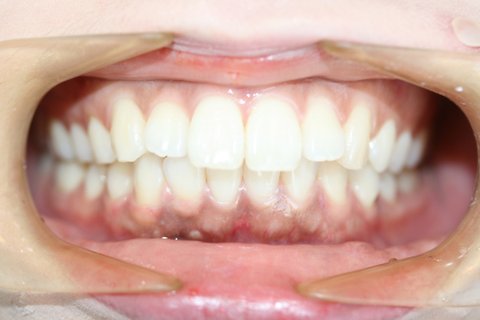

2. 이건 현재 ㅌㅁ치과에서 교정하고있는 피해자...

(첫번째사진이 교정전, 두번째사진이 2년 후임. 엑스레이도 교정 2년 후 사진..)

발치교정은 원래 투명교정으로 안되는 건데 ㅌㅁ치과 상담실장이 무작정 돈보고^^^ 투명교정 할수 있다고 해서 시작했는데 발치공간 안 줄어들어, 어금니 다 드러누워, 과개교합 생겨... 교정치과가 아니라 부작용치과임.